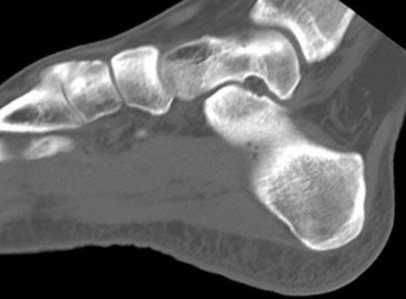

Tarsal coalitions occur when primitive mesenchymal cells fail to differentiate and form the

normal articular separations between the tarsal bones of the hindfoot. Overall incidence is difficult to determine because many affected people are minimally symptomatic or asymptomatic. Symptomatic tarsal coalitions typically present in adolescents as a painful flatfoot; however, there are a number of possible presentations, and occasionally symptoms do not appear until adulthood. Most tarsal coalitions are between the calcaneus and the navicular (CN) and the talus and the calcaneus (TC). Although most TC coalitions are across the middle facet, posterior facet coalitions do occur. Plain radiographic evaluation of suspected tarsal coalition is the mainstay for diagnosis. However, coalitions can be bony or fibrous, and making the diagnosis can be difficult. The addition of CT images to distinguish bony definition and MR images to decipher soft tissue can aid in diagnostics. Bony coalitions appear as definite bony bridging between the bones, while fibrous coalitions are suspected when distortion of the bony anatomy is seen. Bony coalitions are best seen on the oblique view (CN) and Harris axial view (TC). There are a number of secondary signs such as the anteater (AE) sign (elongation of the anterior process of the calcaneus as it extends to the navicular as seen on the lateral view [CN]). talar beaking (traction spur of the talar neck thought to result from abnormal stresses as seen on the lateral view [both CN and TN]), and the “C” sign (a continuous cortical contour from the medial talus to the sustentaculum tali [ST]) as seen on the lateral view (TC). A number of newer signs are not as well known, such as a broad mediolateral dimension of the navicular on the anteroposterior (AP) view (the

navicular is wider than the talar head [CN]), nonvisualization of the middle facet on the lateral view (TC), the brick sign (a normal ST is flat, but a distorted ST is enlarged and curved [CN]), and a tapered lateral navicular bone as seen on the AP view (the medial navicular [CN] is much thicker than the lateral navicular).

Figure 3a shows a flatfoot. Figure 3b shows an MF and TB, but not a C sign. Figure 3c shows a bony irregularity between the calcaneus and the navicular and a WN. Figure 3d shows an MF. Figure 3e shows an MF, but narrowing or loss of the posterior facet. Figures 3f through 3h show medial edema and joint irregularities consistent with a posterior facet coalition.